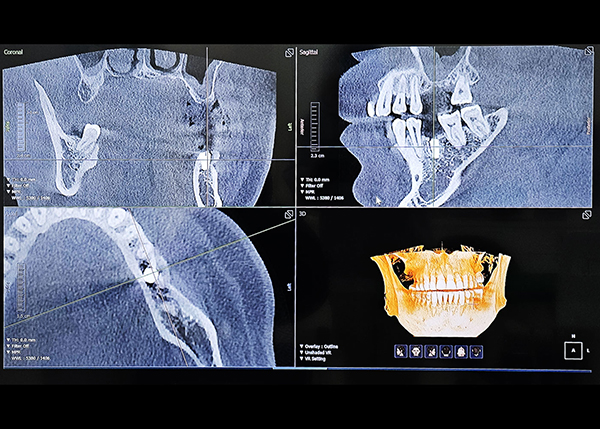

3D CT를 통한 컴퓨터 분석

현재 턱 뼈와 잇몸의 상태를 3차원 입체 영상으로 확인이 가능해

정밀 진단에 따른 오차 없는 수술이 가능